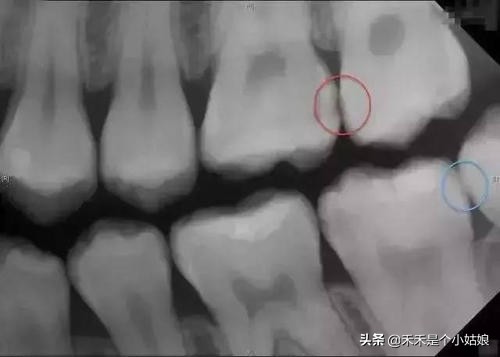

结果出来了,女儿有三颗牙齿需要补,一颗需要根管治疗,于是我跟医生简单沟通了下治疗过程,带着女儿看了下她“牙齿的照片”。这时的她已经开始逐渐放松警惕,医生建议我今天先给她补一颗蛀牙最轻的牙齿,让女儿感受下治疗的过程,不要一次性让她接受太多,导致再次排斥看牙医。在治疗的时候治疗室有电视*放播**动画,护士也给了她一些关于牙齿的玩具,还有在做每一个动作之前都会提前给她讲述下感受,并且让她用手提前感受下治疗器械和器械对她身体带来的感觉,就这样女儿顺利的补了一颗牙,治疗完医生还鼓励性的奖励了几个小贴纸,最后女儿开心的结束了治疗过程,当然走的时候我也兑现了之前的承诺给她买了玩具。完美的结束了第二趟看牙医之旅。